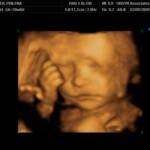

See his beautiful smile!?!Elijah's Ultrasound Pictures taken at 28 weeks.See his little eye opened?!How cute!Another sweet smile!His little foot up against his bottom.

Elijah's Ultrasound Pictures

To see a larger view of the small pictures, let the page finish loading then click on the picture.